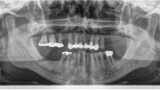

Compromised maxillary dentition treated with Straumann Pro Arch and a digital workflow